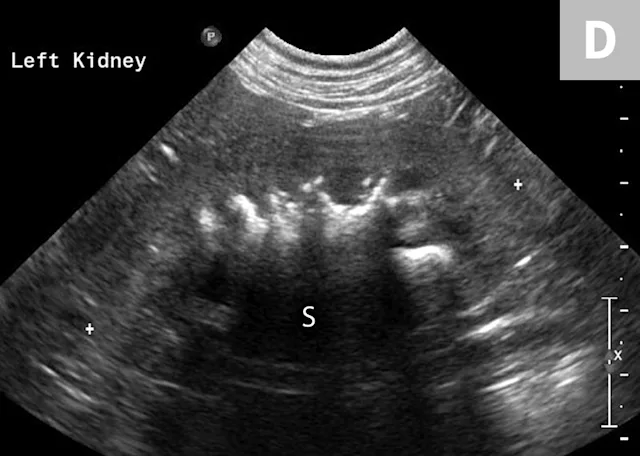

Clinical signs associated with ureteral calculi may range from chronic non-specific signs to acute or chronic renal failure. The presence of hydronephrosis can be highly suggestive of a ureteral obstruction (Figure 6).

Mild to moderate right hydronephrosis and proximal ureteral dilation in a Dalmatian.